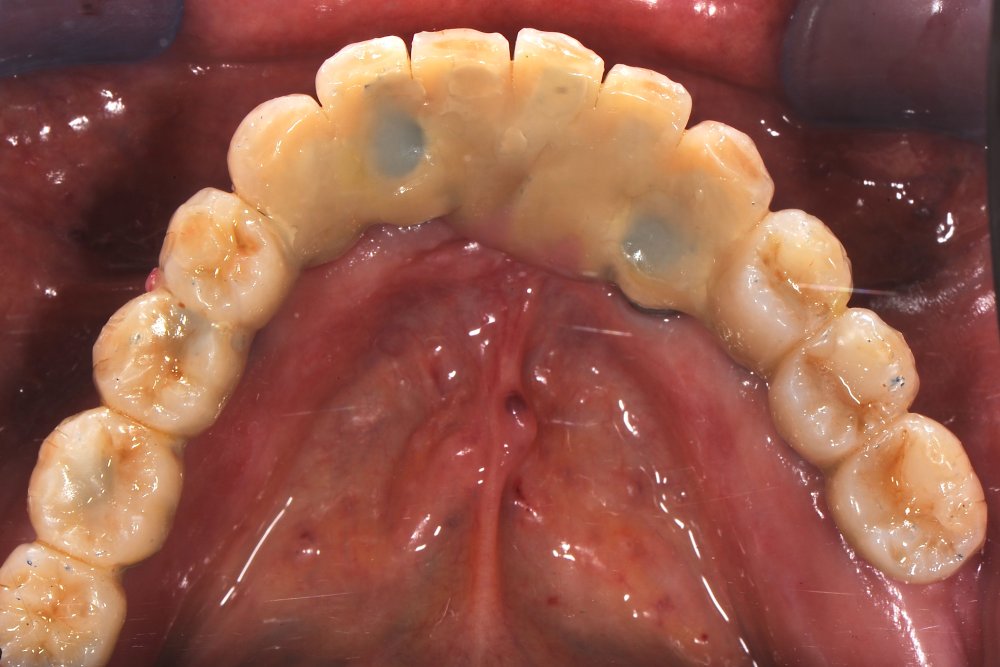

Riabilitazione totale inferiore e superiore su impianti in Metallo - Composito

il paziente si presentava con una situazione compromessa nelle due arcate, il piano riabilitativo concordato è stato quello di una protesi totale provvisoria superiore (con futuro carico immediato), e di una protesi in metallo - composito ( LUNA WING ) differita.